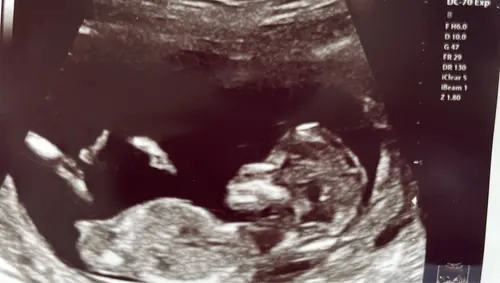

Is hier iets op te zien? 13.0 precies.

Kan iemand hier iets herkennen? Echo van 13+5

Ik vind ze alle 3 best onduidelijk